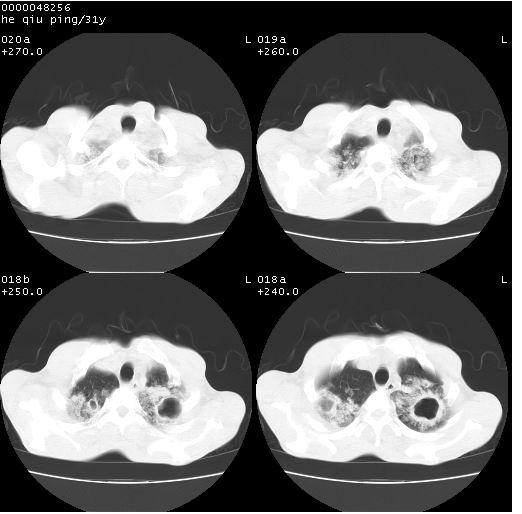

标题: CT13402:M,31Y。肺结核伴空洞形成?

咳嗽半月余,消瘦体质,呼吸音弱。无其他病史。cr:肺转移瘤待。

双上肺多发空洞,双飞散在分布大小不一的片状结高密度影节状大片状高密度影。符合结合肉芽肿形成及空洞形成。

双侧弥漫性病变,双上叶尖后段、下叶北段见多个空洞,多见于结核感染。右中叶及双下叶斑片状,结节状影,考虑为肉芽肿形成及支气管播散。但由于患者消瘦体质,抵抗力低下,若继发感染,如金葡菌肺炎也有可能。